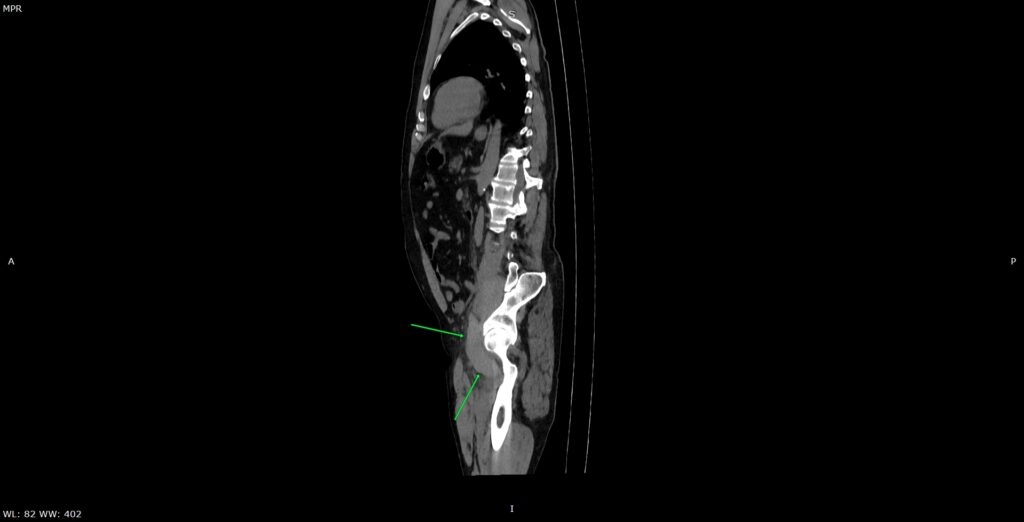

Figura 2: reconstrucție oblic sagitală din achiziție CT fără contrast posttraumatic imediat

Discuţie caz nr 134: Pe imaginile achiziționate fără substanță de contrast se remarcă creștere marcată de volum a muschiului ilio-psoas drept în două treimi distale cu evidențierea unei plaje întinse cu densități sangvine ce sugerează prezența unui hematom posttraumatic; nu se evidențiază traiecte de fractură. Achiziția de control după 22 de luni evidențiază reducerea grosimii corpului muscular ilio-psoas drept cu încărcare grăsoasă care, pe alocuri, afectează aproape complet corpul muscular.